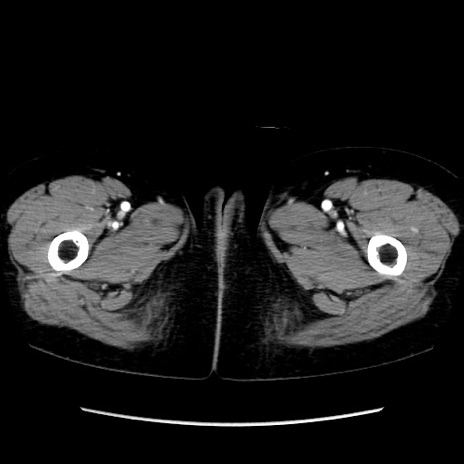

症例32(横断像)

【症例】40歳代 女性

【主訴】上腹部痛、嘔気・嘔吐

【現病歴】約9時間前頃から急に上腹部痛、嘔気、嘔吐が出現。改善しないため救急要請。

【既往歴】子宮頚癌(広汎子宮全摘術、放射線療法)、腸閉塞

【身体所見】腹部:平坦、軟、腸雑音亢進、上腹部を中心に腹部全体に圧痛あり。

【データ】WBC 8400、CRP 0.03